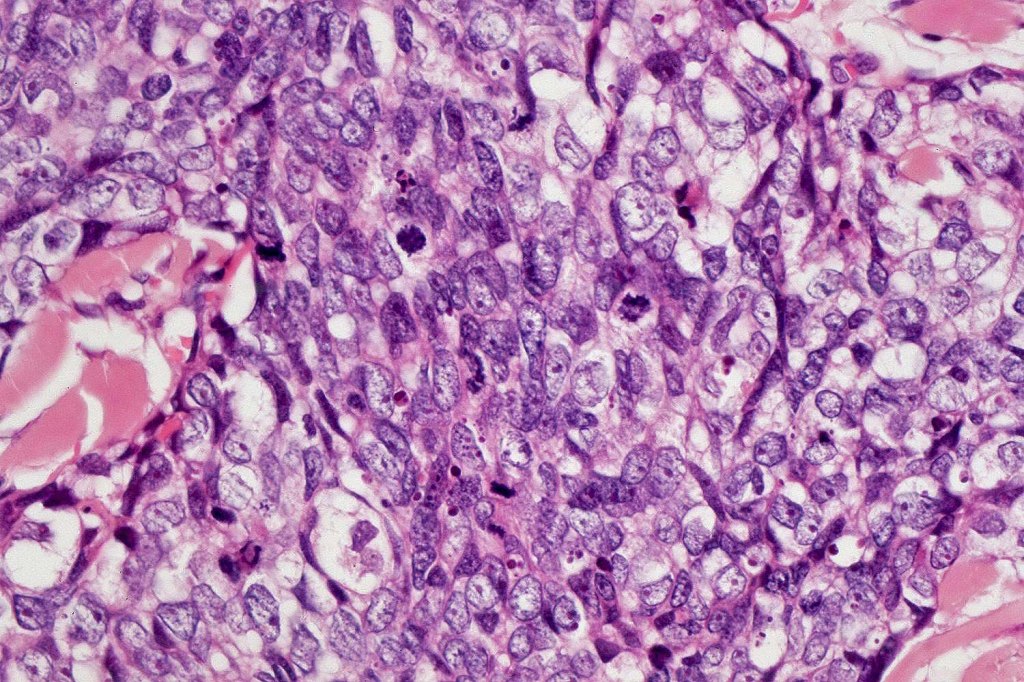

•Well differentiated lobular growth pattern though to a poorly differentiated tumor often showing a diffuse, infiltrating border which may extend into the subcutaneous fat

•Well differentiated examples can be deceptive unless one looks carefully for pleomorphism, necrosis, excessive mitotic activity and abnormal mitoses. Be careful diagnosing sebaceous adenoma, particularly large examples arising in the elderly

•Tumors are composed of an admixture of darkly staining basaloid cells with hyperchromatic or vesicular nuclei and more obvious sebaceous cells with eosinophilic, bubbly, multivacuolated cytoplasm frequently indenting the nucleus (scalloped)

•Often mitoses are numerous and abnormal forms evident

•May be graded into well, moderate & poorly differentiated categories. I am not sure that this has any great value